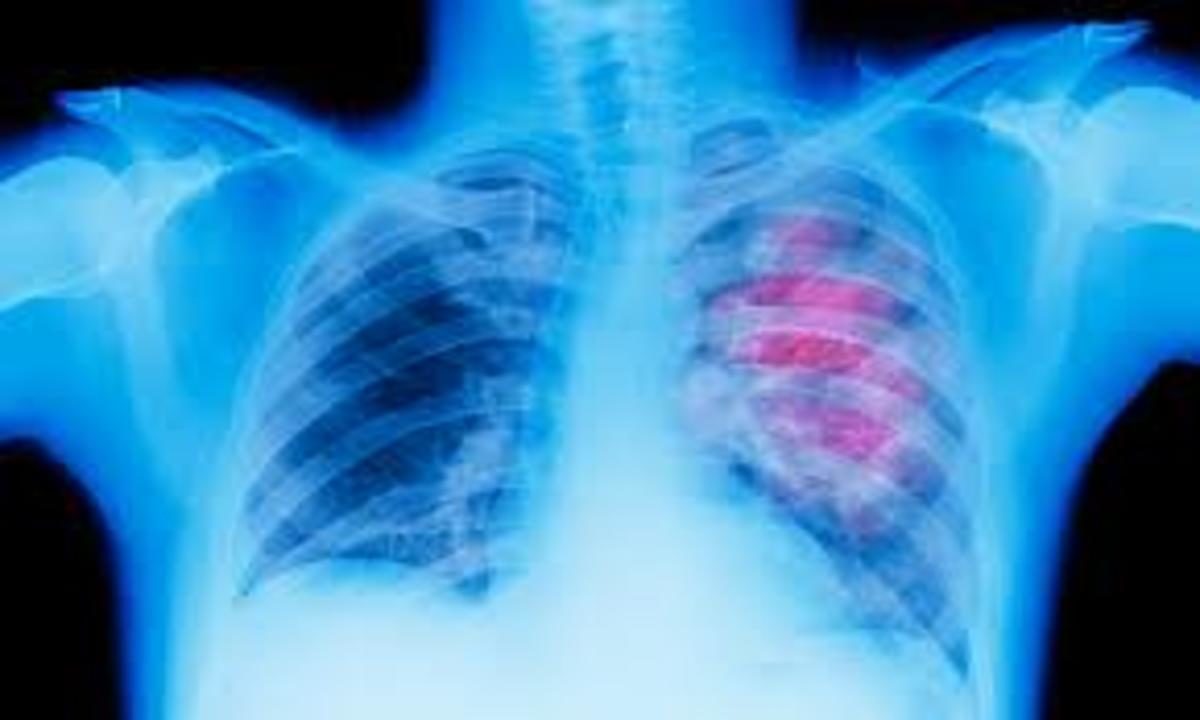

Νέοι δρόμοι στην διάγνωση του καρκίνου του πνεύμονα

Η Ventana Medical Systems, Inc. (Ventana), μέλος του Ομίλου Roche, ανακοίνωσε πρόσφατα την έγκριση της μεθόδου VENTANA ALK (D5F3) CDx Assay από τον Οργανισμό Τροφίμων και Φαρμάκων των ΗΠΑ (FDA) ως συνοδευτική διαγνωστική εξέταση, που βοηθά στην αναγνώριση ασθενών με καρκίνο του πνεύμονα που μπορούν να επιλεγούν για να λάβουν την εγκεκριμένη από τον FDA, στοχευμένη θεραπεία με κριζοτινίμπη της Pfizer.